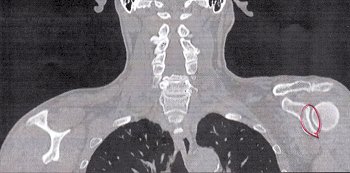

とりあえずCTスキャン。

で、頂きましたのが、その一部のこれらの画像なんです(^.-)☆

特に痛みの原因となるようなモノは見当たらず、強いて言えば『老化現象』との事でありました。